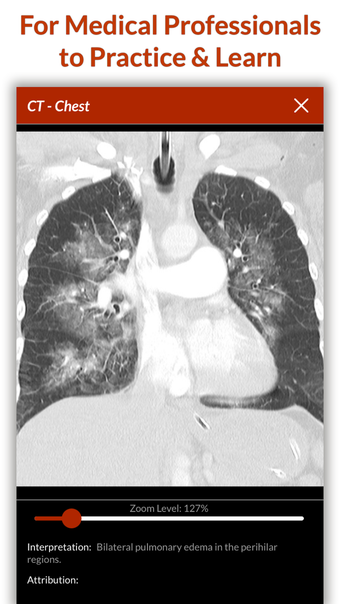

Full Code - Emergency Medicine Simulation è un'applicazione Android sviluppata da Minerva Medical Simulation Inc. È una versione completa con licenza di un'applicazione di stile di vita che rientra nella sottocategoria medica. È un'applicazione di simulazione intuitiva, mobile-first che offre oltre 160 casi virtuali realistici e un'interfaccia coinvolgente simile a un gioco, preferita dai professionisti medici di tutto il mondo. L'applicazione è progettata per aiutare gli studenti e i professionisti medici a acquisire fiducia nel trattamento di casi complessi e offre 0,5 crediti AMA PRA Categoria 1™ per ogni caso Full Code giocato con Full Code Pro+CME.

L'applicazione consente agli utenti di esercitarsi in diagnosi cliniche rare e rischiose in un ambiente sicuro in modo da poter affrontare casi complessi del mondo reale con fiducia. Con oltre 160 casi in 31 specialità, Full Code consente di esercitarsi in simulazioni mediche on-demand ogni volta che si ha una pausa, ovunque ci si trovi. L'applicazione è ottimizzata per la portabilità e l'accessibilità ed è disponibile su qualsiasi dispositivo mobile, desktop o tablet. Full Code è accreditato attraverso l'ACCME e, con la sua sottoscrizione PRO+CME, gli utenti possono completare i loro requisiti di formazione medica continua (CME) con sfide di simulazione flessibili e piacevoli. È un'applicazione eccellente per i professionisti medici che vogliono migliorare le proprie competenze e acquisire fiducia nel gestire casi complessi.